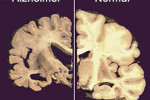

Anche i medici ritengono questa scelta alimentare ottima per combattere patologie come l’obesità, il diabete e quelle cardiovascolari. A Milano poi è stata avanzata la proposta di inserire nelle mense scolastiche un giorno con il menù vegano. Lo è già il mercoledì della Lav: la Lega antivivisezione ha infatti già istituito la giornata veg in cui partendo dalla tavola si pensa al pianeta, alla salute e agli animali. Se tutta la popolazione adulta adottasse il mercoledì veg il risparmio sarebbe pari a miliardi di chilometri in meno percorsi in auto e miliardi di litri d’acqua preservati. Perché per fare un kg di carne si consumano 15.500 litri d’acqua e ogni hamburger comporta la distruzione di cinque metri quadrati di foreste. Mangiare veg significa anche mangiare tutti: la scelta è anche contro la fame nel mondo perché il 50% dei cereali e il 90% della soia prodotti al mondo servono solo a nutrire gli animali d’allevamento. E il 4 ottobre in tutta Italia si è celebrata la Prima notte veg: promossa dalla casa editrice Sonda, da 25 anni punto di riferimento dei vegani, ha visto coinvolti oltre cento ristoratori, anche non specializzati, che da nord a sud hanno unito la penisola per una festa in simultanea di consapevolezza etica. Un appuntamento destinato a diventare fisso. Il primo novembre intanto in tutto il pianeta si celebra la Giornata Mondiale Vegan, un’occasione di incontro e dibattito anche nelle scuole, per promuovere i benefici di questa scelta.